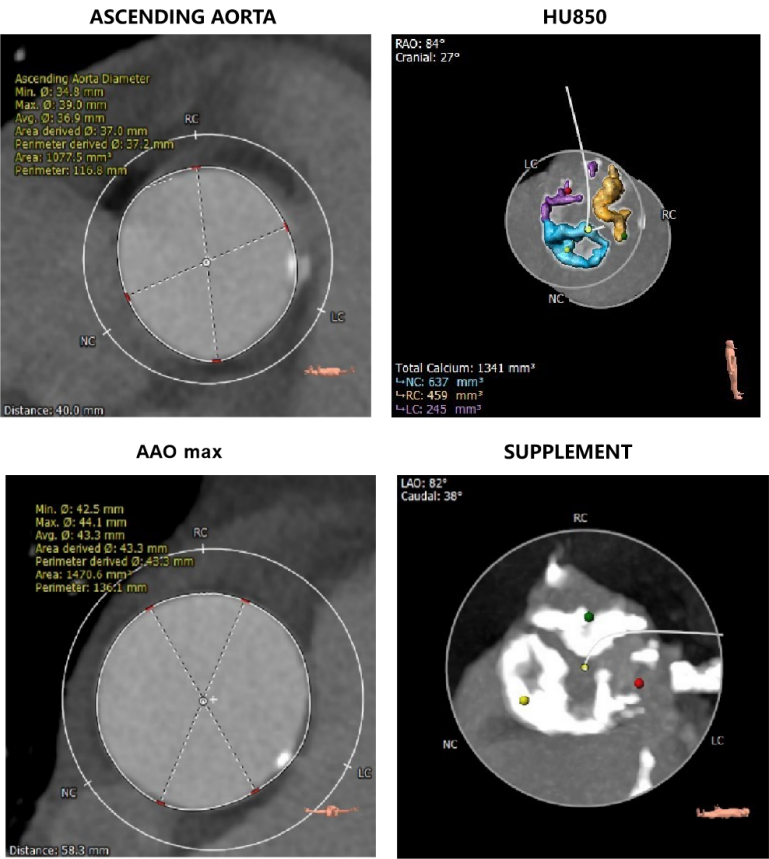

CT数据显示该患者为三叶三窦式主动脉瓣。

主动脉瓣瓣环周长77.0mm,平均周长径 24.5mm;LVOT周长89.1mm,平均周长径28.4mm;SOV:28.5mm*29.3mm*32.0mm;STJ平面周长94.6mm;瓣叶增厚,瓣上钙化明显,HU850积分1341mm³, HU560积分2499mm³,升主动脉最大直径44.1mm。

左冠开口高度11.0mm,右冠开口高度15.0mm,左冠高度较低,根据瓦氏窦内径和瓣叶长度综合判断,左冠堵塞风险不高;右冠瓣叶长度较长,存在一定封堵风险,合并患者原有冠脉疾病,考虑右冠灌注不良风险较高;左室腔增大,心室壁未见明显增厚。